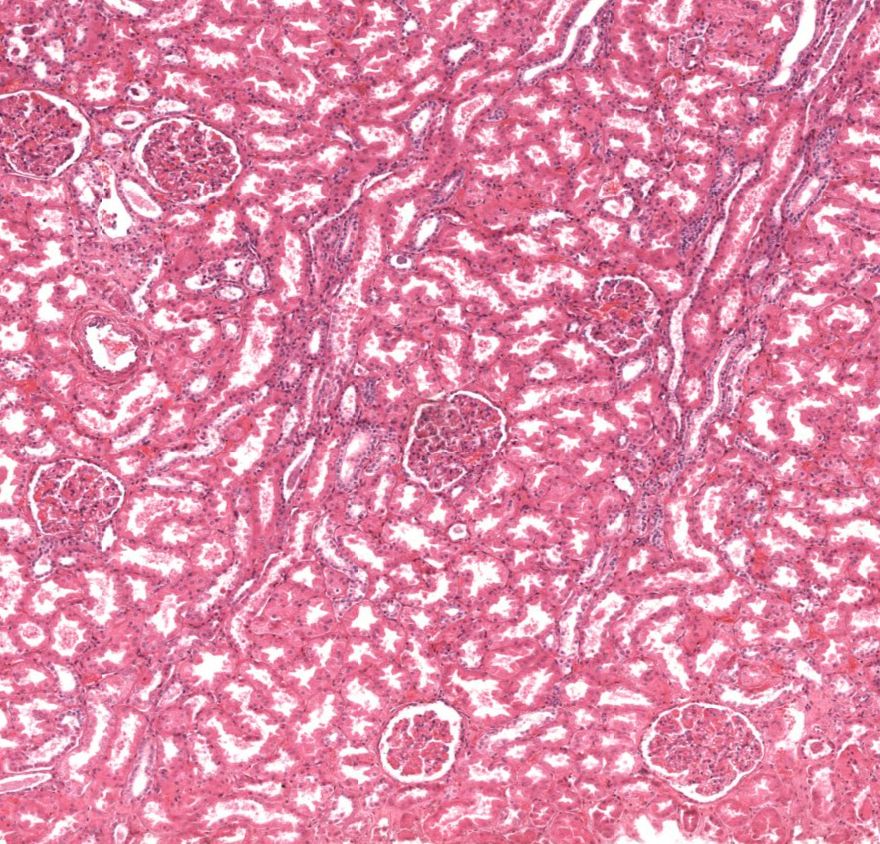

Córtex renal

Córtex renal

Córtex renal